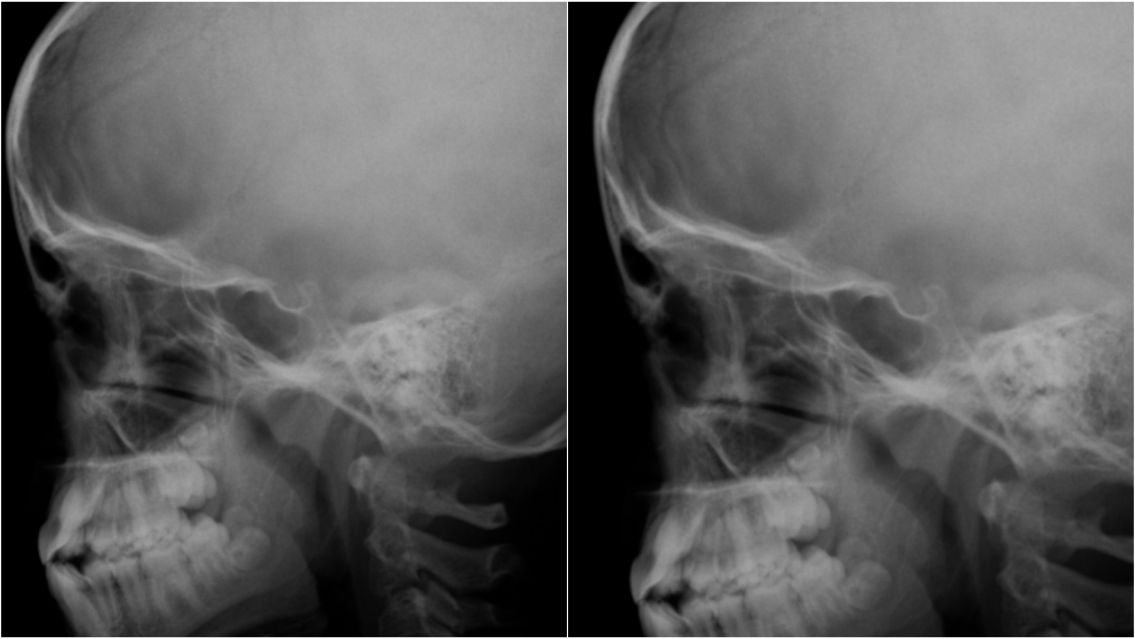

Sin embargo, al intentar limpiar la zona afectada, los profesionales se encontraron con un cuadro mucho más grave del esperado: la infección llevaba varias semanas avanzando y las larvas habían comenzado a destruir tejido blando e incluso perforado parte del hueso del cráneo.

Según explicó el pediatra Flavio Serra, el caso corresponde a una miasis foruncular, una enfermedad provocada por moscas que depositan huevos en la piel. "Las larvas se desarrollan dentro del tejido y pueden generar lesiones profundas. En este caso ya había compromiso óseo", detalló el médico a El Litoral.